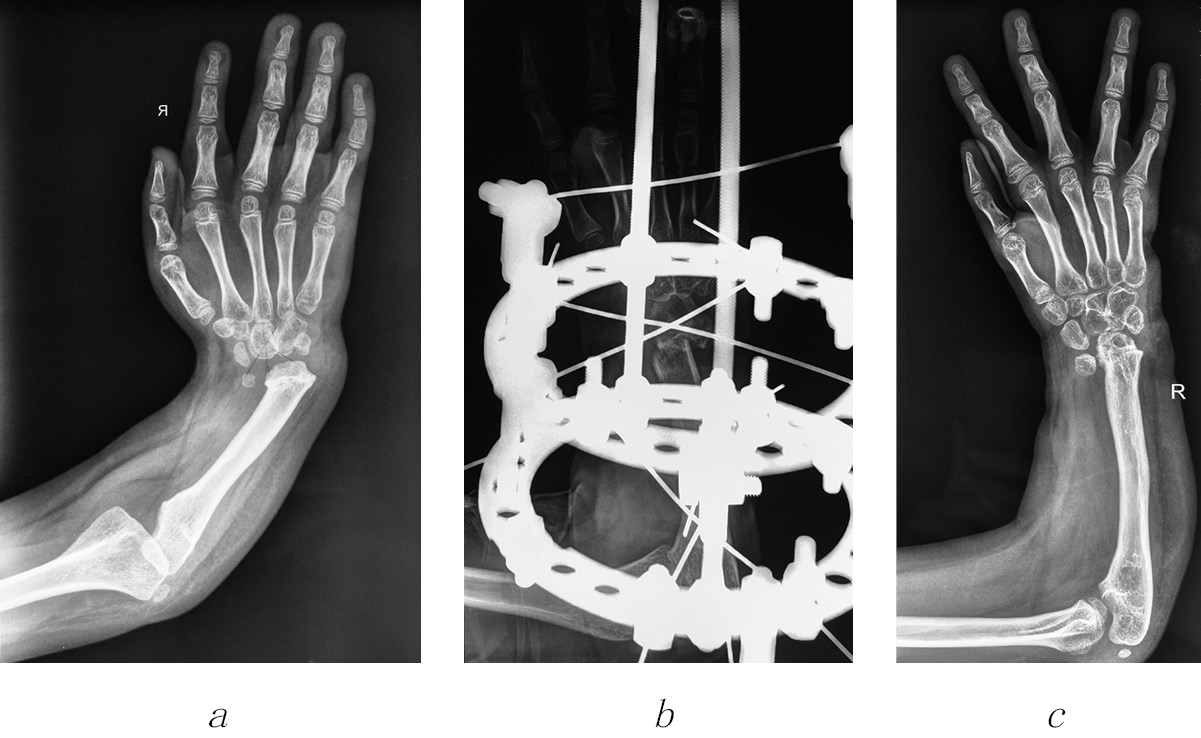

A clinical example of surgical treatment of the group 3 patient (Fig. 2)

Fig. 2. Radiograph of the upper limb of patient L., 6 years old, before elongation of the ulnar bone (a), after osteotomy (b) and after 2 years (c)

Patient L., 6 years old, was admitted to the department with a diagnosis of TAR syndrome, congenital bilateral radial clubhand, and hypoplasia of fingers I. The previous surgery included centering of both right and left hands. Clinical examination revealed shortening of both forearms, aplasia of the radial bones, palmar-radial deviation of the right hand by 40°, the hand was impossible to bring to the middle position passively, and hypoplasia of the fingers I was also reported (Fig. 2, a). Given the marked deviation of the hand, we decided to perform cup-and-ball osteotomy of the right ulnar bone in the lower third. The postoperative period was uneventful. The ulnar bone was elongated by 3.5 cm. The palmar-radial deviation of the hand was corrected up to 35°.

A clinical examination after two years (Fig. 2, c) revealed that radial deviation of the hand was up to 10°. The child served herself and did not complain actively. Her parents were satisfied with the result. Subsequently, the ulnar bone was elongated to the left.